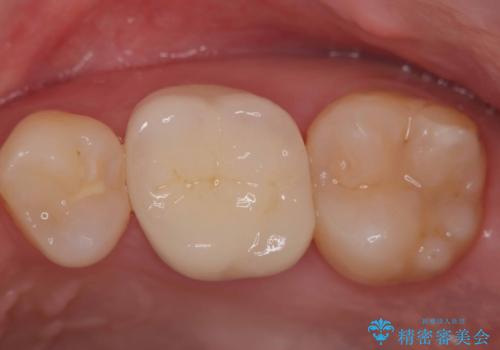

根管治療を行ったのち、症状改善を認めオールセラミッククラウンにて修復治療を行いました。

根管治療にはラバーダムシートをつけて行うことが大切です。マイクロスコープを使用し治療を行いました。治療後、歯の痛みは消失し、とても満足していただきました。

根管治療を行った歯は、再発防止や残された歯質を守るため、クラウンによる補綴治療が必要となります。